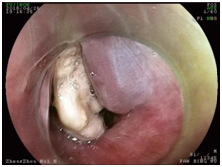

取出卡在食道的枣核势在必行,谢立群对范大爷手术风险进行仔细评估后,决定为范大爷急诊全麻下行胃镜异物取出术。

经过紧张的准备,手术顺利实施。手术过程中发现在食管距门齿17厘米处,也是食管上段最狭窄的地方,一颗大枣核嵌顿,枣核两端已深深扎入食管壁内。